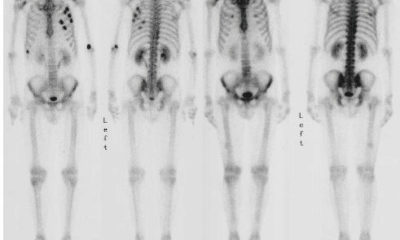

Костная сцинтиграфия или сканирование костной ткани проводится для того, чтобы исключить опухолевый процесс в костях.